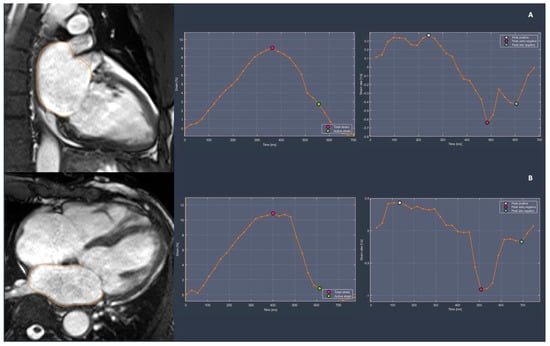

3.2.2. Left Atrial Function